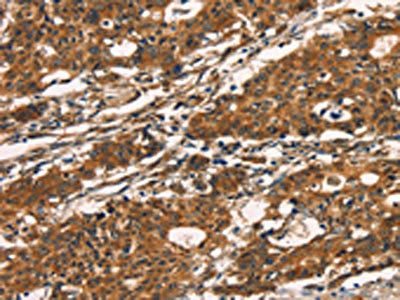

The image on the left is immunohistochemistry of paraffin-embedded Human gastic cancer tissue using CSB-PA073427(KLRC1 Antibody) at dilution 1/20, on the right is treated with fusion protein. (Original magnification: ×200)

The image on the left is immunohistochemistry of paraffin-embedded Human thyroid cancer tissue using CSB-PA073427(KLRC1 Antibody) at dilution 1/20, on the right is treated with fusion protein. (Original magnification: ×200)